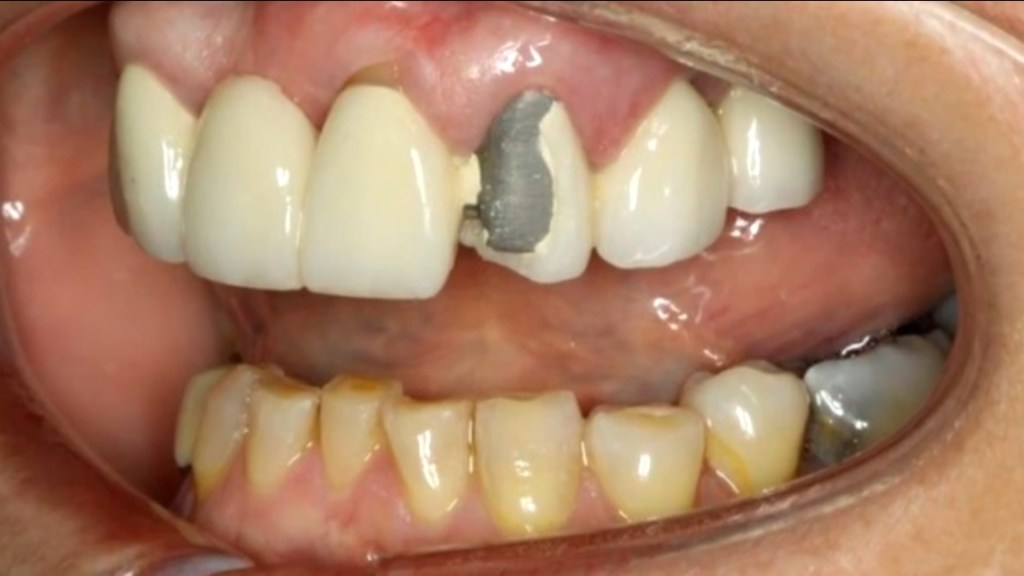

3️⃣ 假牙破裂、崩角(全瓷牙也可能)

植牙假牙雖然堅固,但並非不會破。

常見原因:

• 咬到骨頭、冰塊、硬果仁

• 夜磨牙

• 假牙咬合位置受力不平均

若破損較小可修補;破損嚴重時可能需要重做。